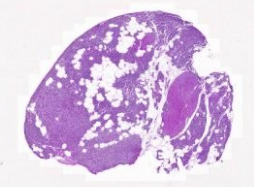

The slides below show a rodent thyroid at three different levels of functional activity:

- 218_NORM - euthyroid state [DigitalScope]

- 218_HYPO - hypoactive state due to hypophysectomy [DigitalScope]

- 218_HYPER - hyperactive state due to treatment with the drug thiouracil. [DigitalScope]

Compare the tissue shown in each slide –the variation is not overwhelming since the experiments were performed conservatively, but you should be able to see some differences in epithelial cell height and in the size of the follicular lumens. Look first at the normal thyroid [DigitalScope] to get a baseline.

Hypoactive thyroid follicular cells [DigitalScope]

Now, look at the hypoactive thyroid gland caused by removal of the pituitary gland (hypophysectomy). After hypophysectomy there is no stimulation by TSH, so the follicular epithelial cells become reduced in height and the colloid in the lumen is abundant, since it is not being resorbed to make thyroid hormones. In these hypoactive slides, C-cells [example] are more obvious as these cells are fully functional and not dependent on TSH.